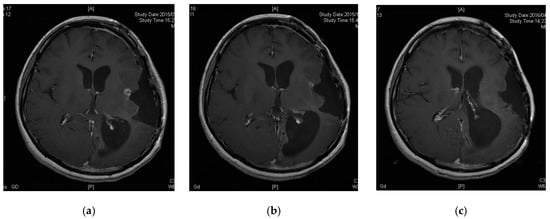

3.5. A Case of CR following Peptide Vaccination

Patient 6 was a 33-year-old female diagnosed with diffuse astrocytoma (grade 2) four years prior. Her tumor was enlarged and removed twice, followed by treatment with TMZ and radiation therapy for the preceding 12 months. The pathological diagnosis was anaplastic oligoastrocytoma (grade 3, MGMT unmethylated, IDH mutant and no 1p19q codeletion). However, her tumor recurred and could not be removed as it was located in a functional area (Figure 2a). She was thus enrolled in our study. Her tumor decreased in size three months after vaccine initiation and disappeared nine months after enrollment (Figure 2b,c). Thirty-eight months after the initiation of peptide vaccination, the patient remains free of tumor recurrence.

Figure 2.

Contrast-enhanced magnetic resonance images of Patient 6. (a) Tumor had recurred in a functional area; (b) tumor was decreased 3 months after enrollment; (c) tumor disappeared 9 months after enrollment.

One HGG patient (Patient 6) experienced objective clinical tumor regression (response rate of this vaccine treatment was 10%). Furthermore, it is noteworthy that this patient exhibited PR at week six and CR at week nine. CTLs specific for all six antigens were strongly induced in the patients, suggesting that this CTL response might contribute to the observable effect.